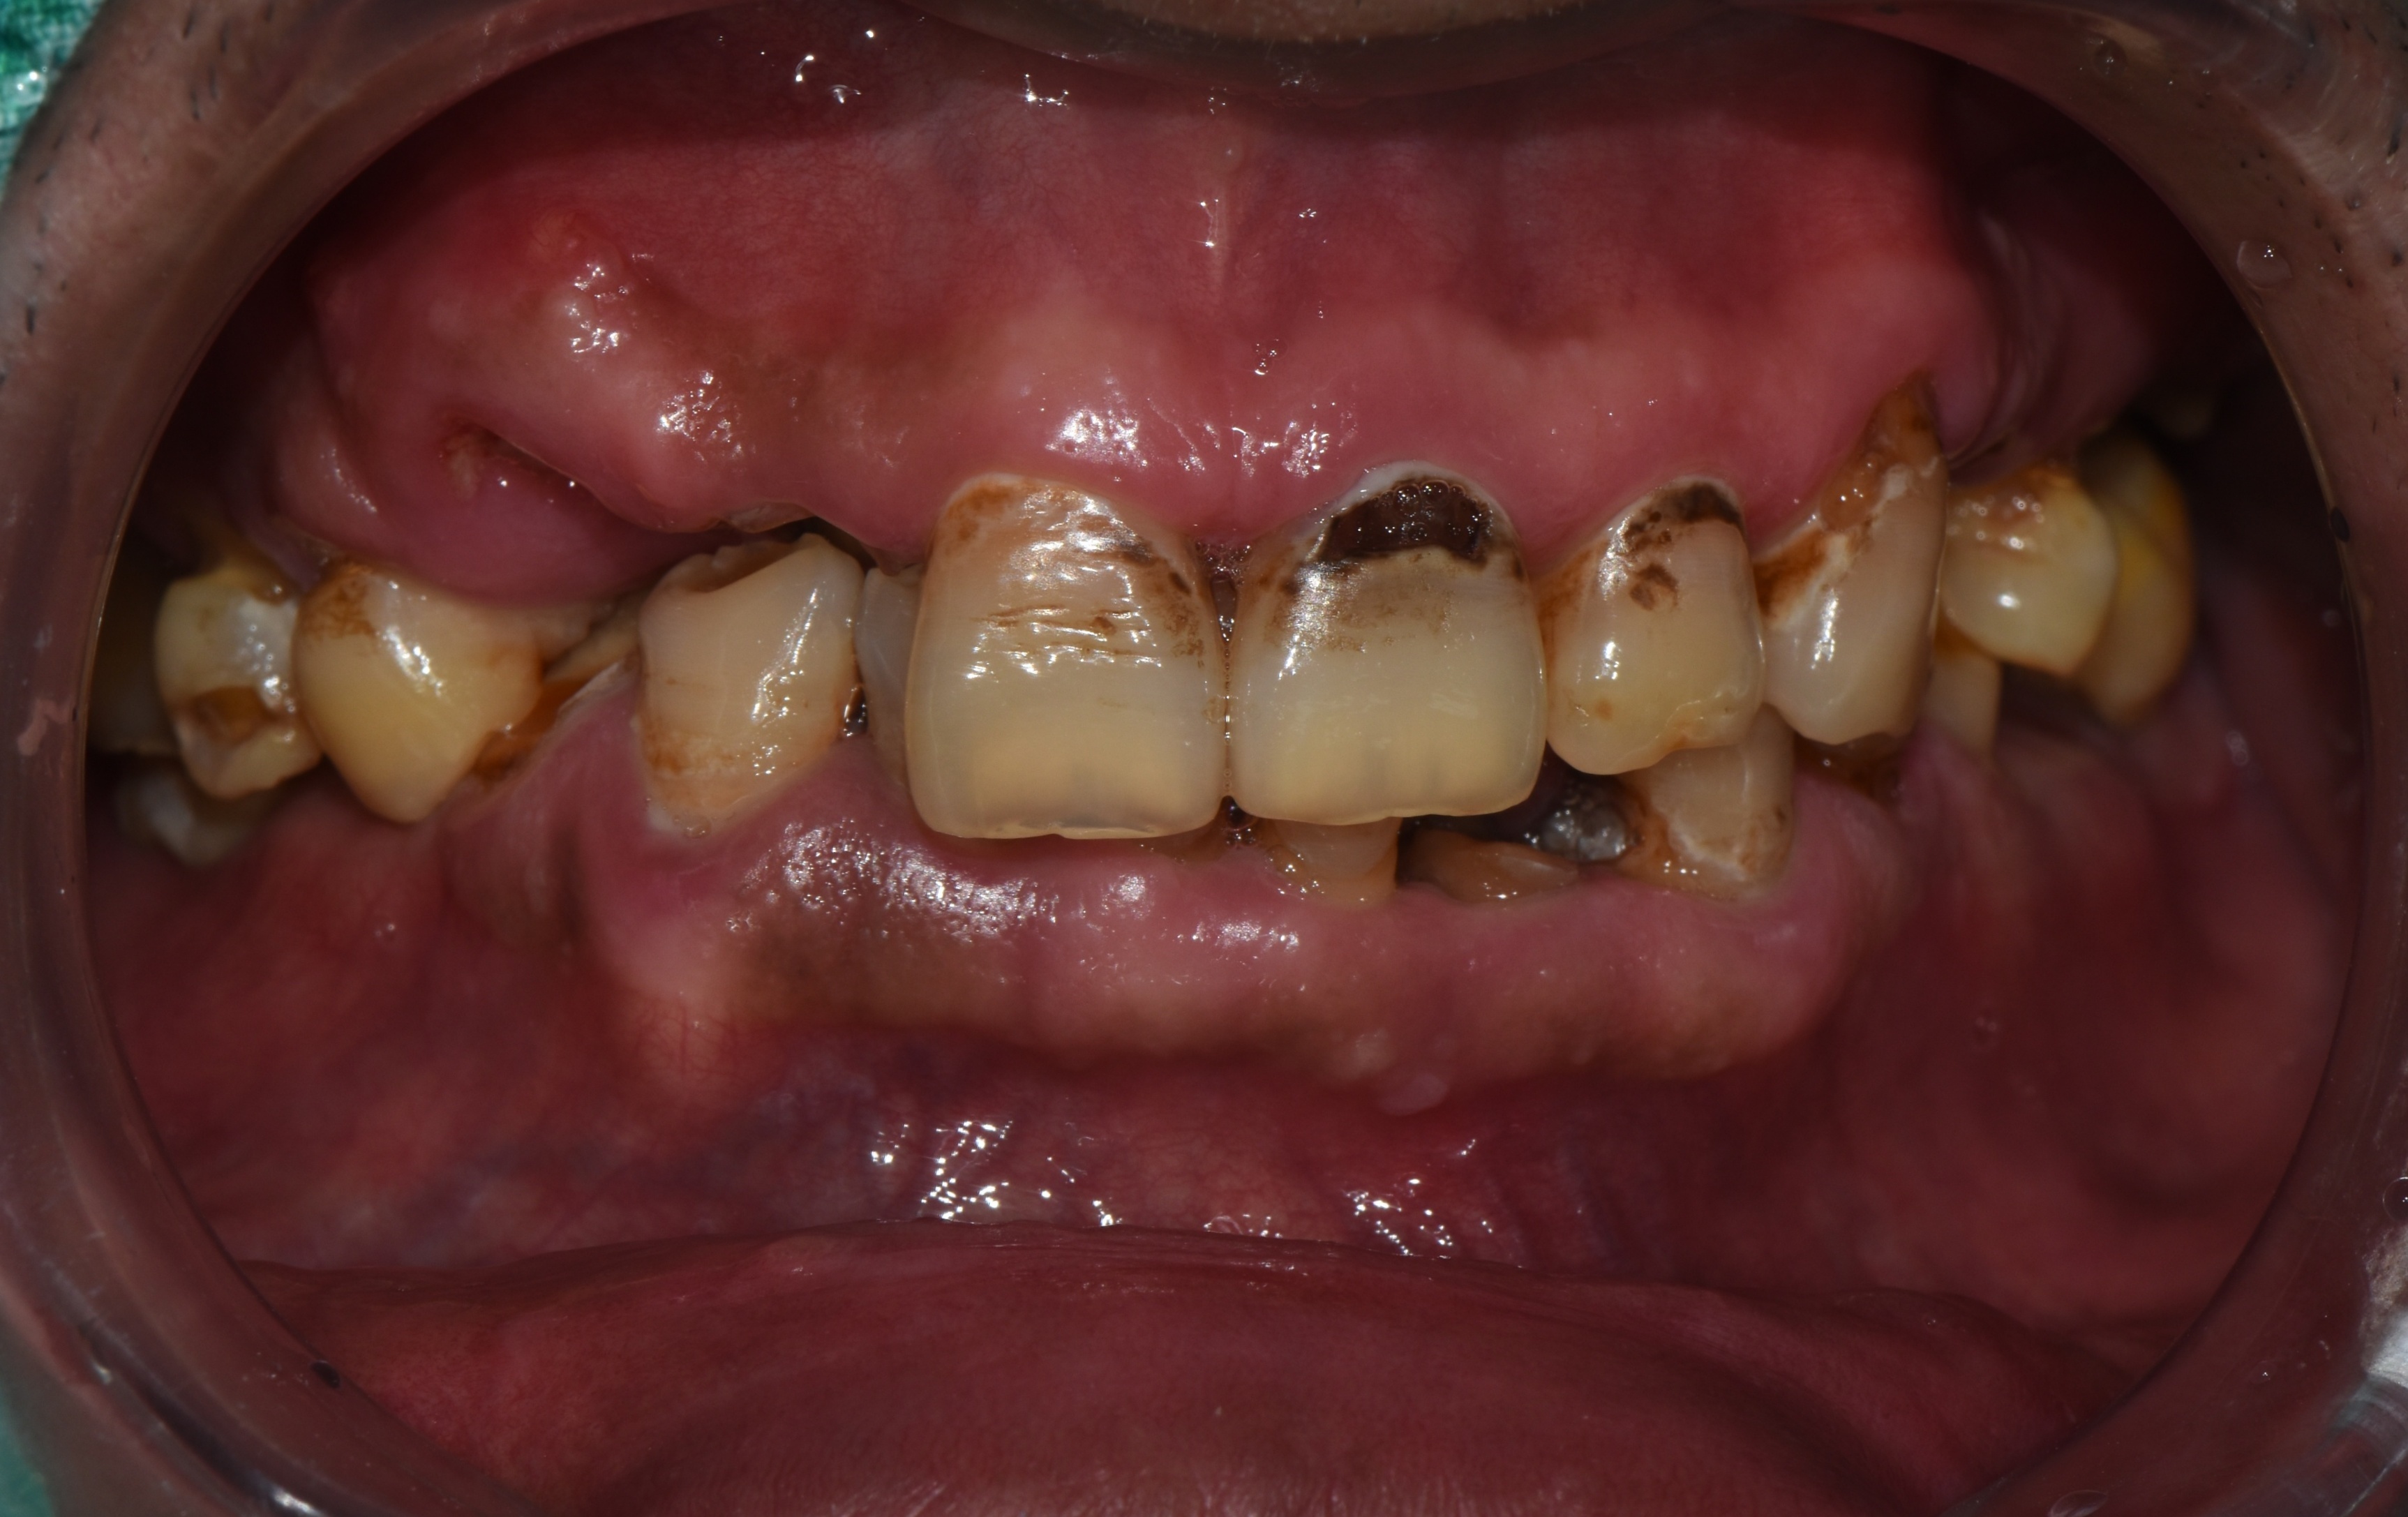

촬영일시: 2025.05.27